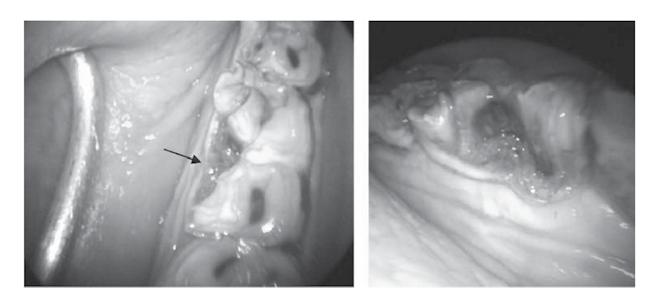

Endoscopy of the oral canal utilizes a special camera with a light to enhance the visualization of the oral cavity. The image is also magnified which helps detect subtle changes in hard to view areas. The video can be recorded for documentation and it allows the owner to see what the veterinarian is seeing. Endoscopy can also be utilized for examining the nasal passage and the back of the throat.

Amir is a horse that received routine extractions of molars and developed nasal discharge. Despite veterinary intervention, he continued to worsen. The radiograph below shows the area of interest as well as the CT images used for diagnosis of the extent of the problem as well as surgical planning. You can see how much more detailed information is available from a CT examination vs plain radiographs. To read and an image from a normal CT scan on the right. more about Amir, find his full case study on our website at https://animalimaging.net/equine-sinusitis/.